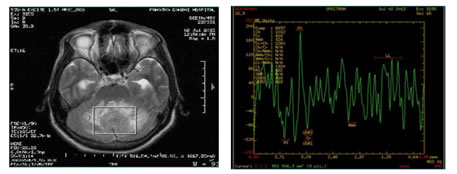

Figure 2: 65 year old man with Meningioma in right high parietal region showing alanine peak at 1.5 ppm on MR Spectroscopy